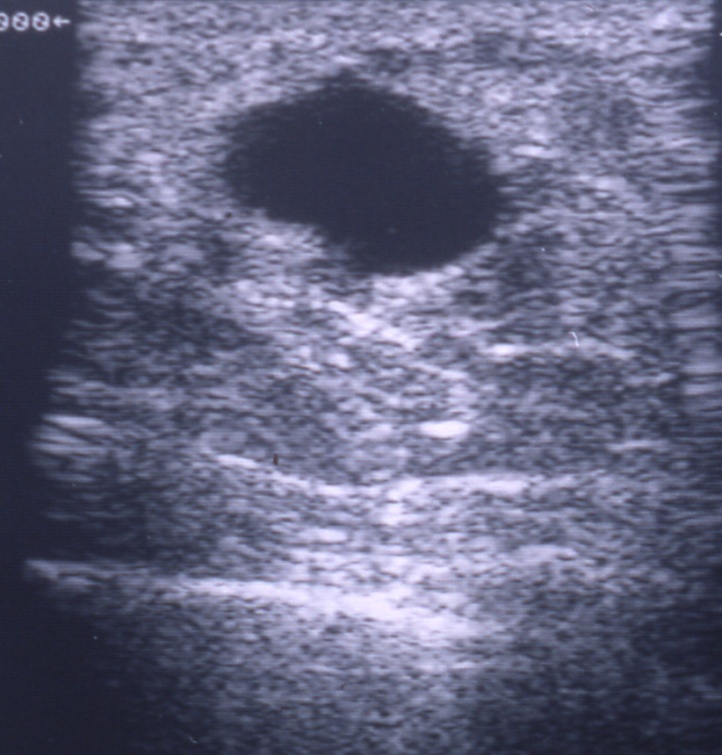

Breast cysts are fluid-filled sacs inside the breast. They are usually noncancerous simple cysts (benign). You may have one or multiple breast cysts. A breast cyst often feels like a grape or a water-filled balloon, but sometimes a breast cyst feels firm. Breast cysts tend to be caused by hormonal influences (eostrogen).

Breast cysts don’t require treatment unless a cyst is large and painful or uncomfortable. In that case, draining the fluid from a breast cyst can ease symptoms. It can be drained by aspirating the cyst with a fine needle. Removing the fluid may reduce pressure and pain for some time as well as being diagnostic. Usually clear, yellow or greenish fluid is not dangerous.

A solid component to the cyst is termed a complex cyst. This sometimes requires a biopsy to ascertain whether it is associated with a cancer.